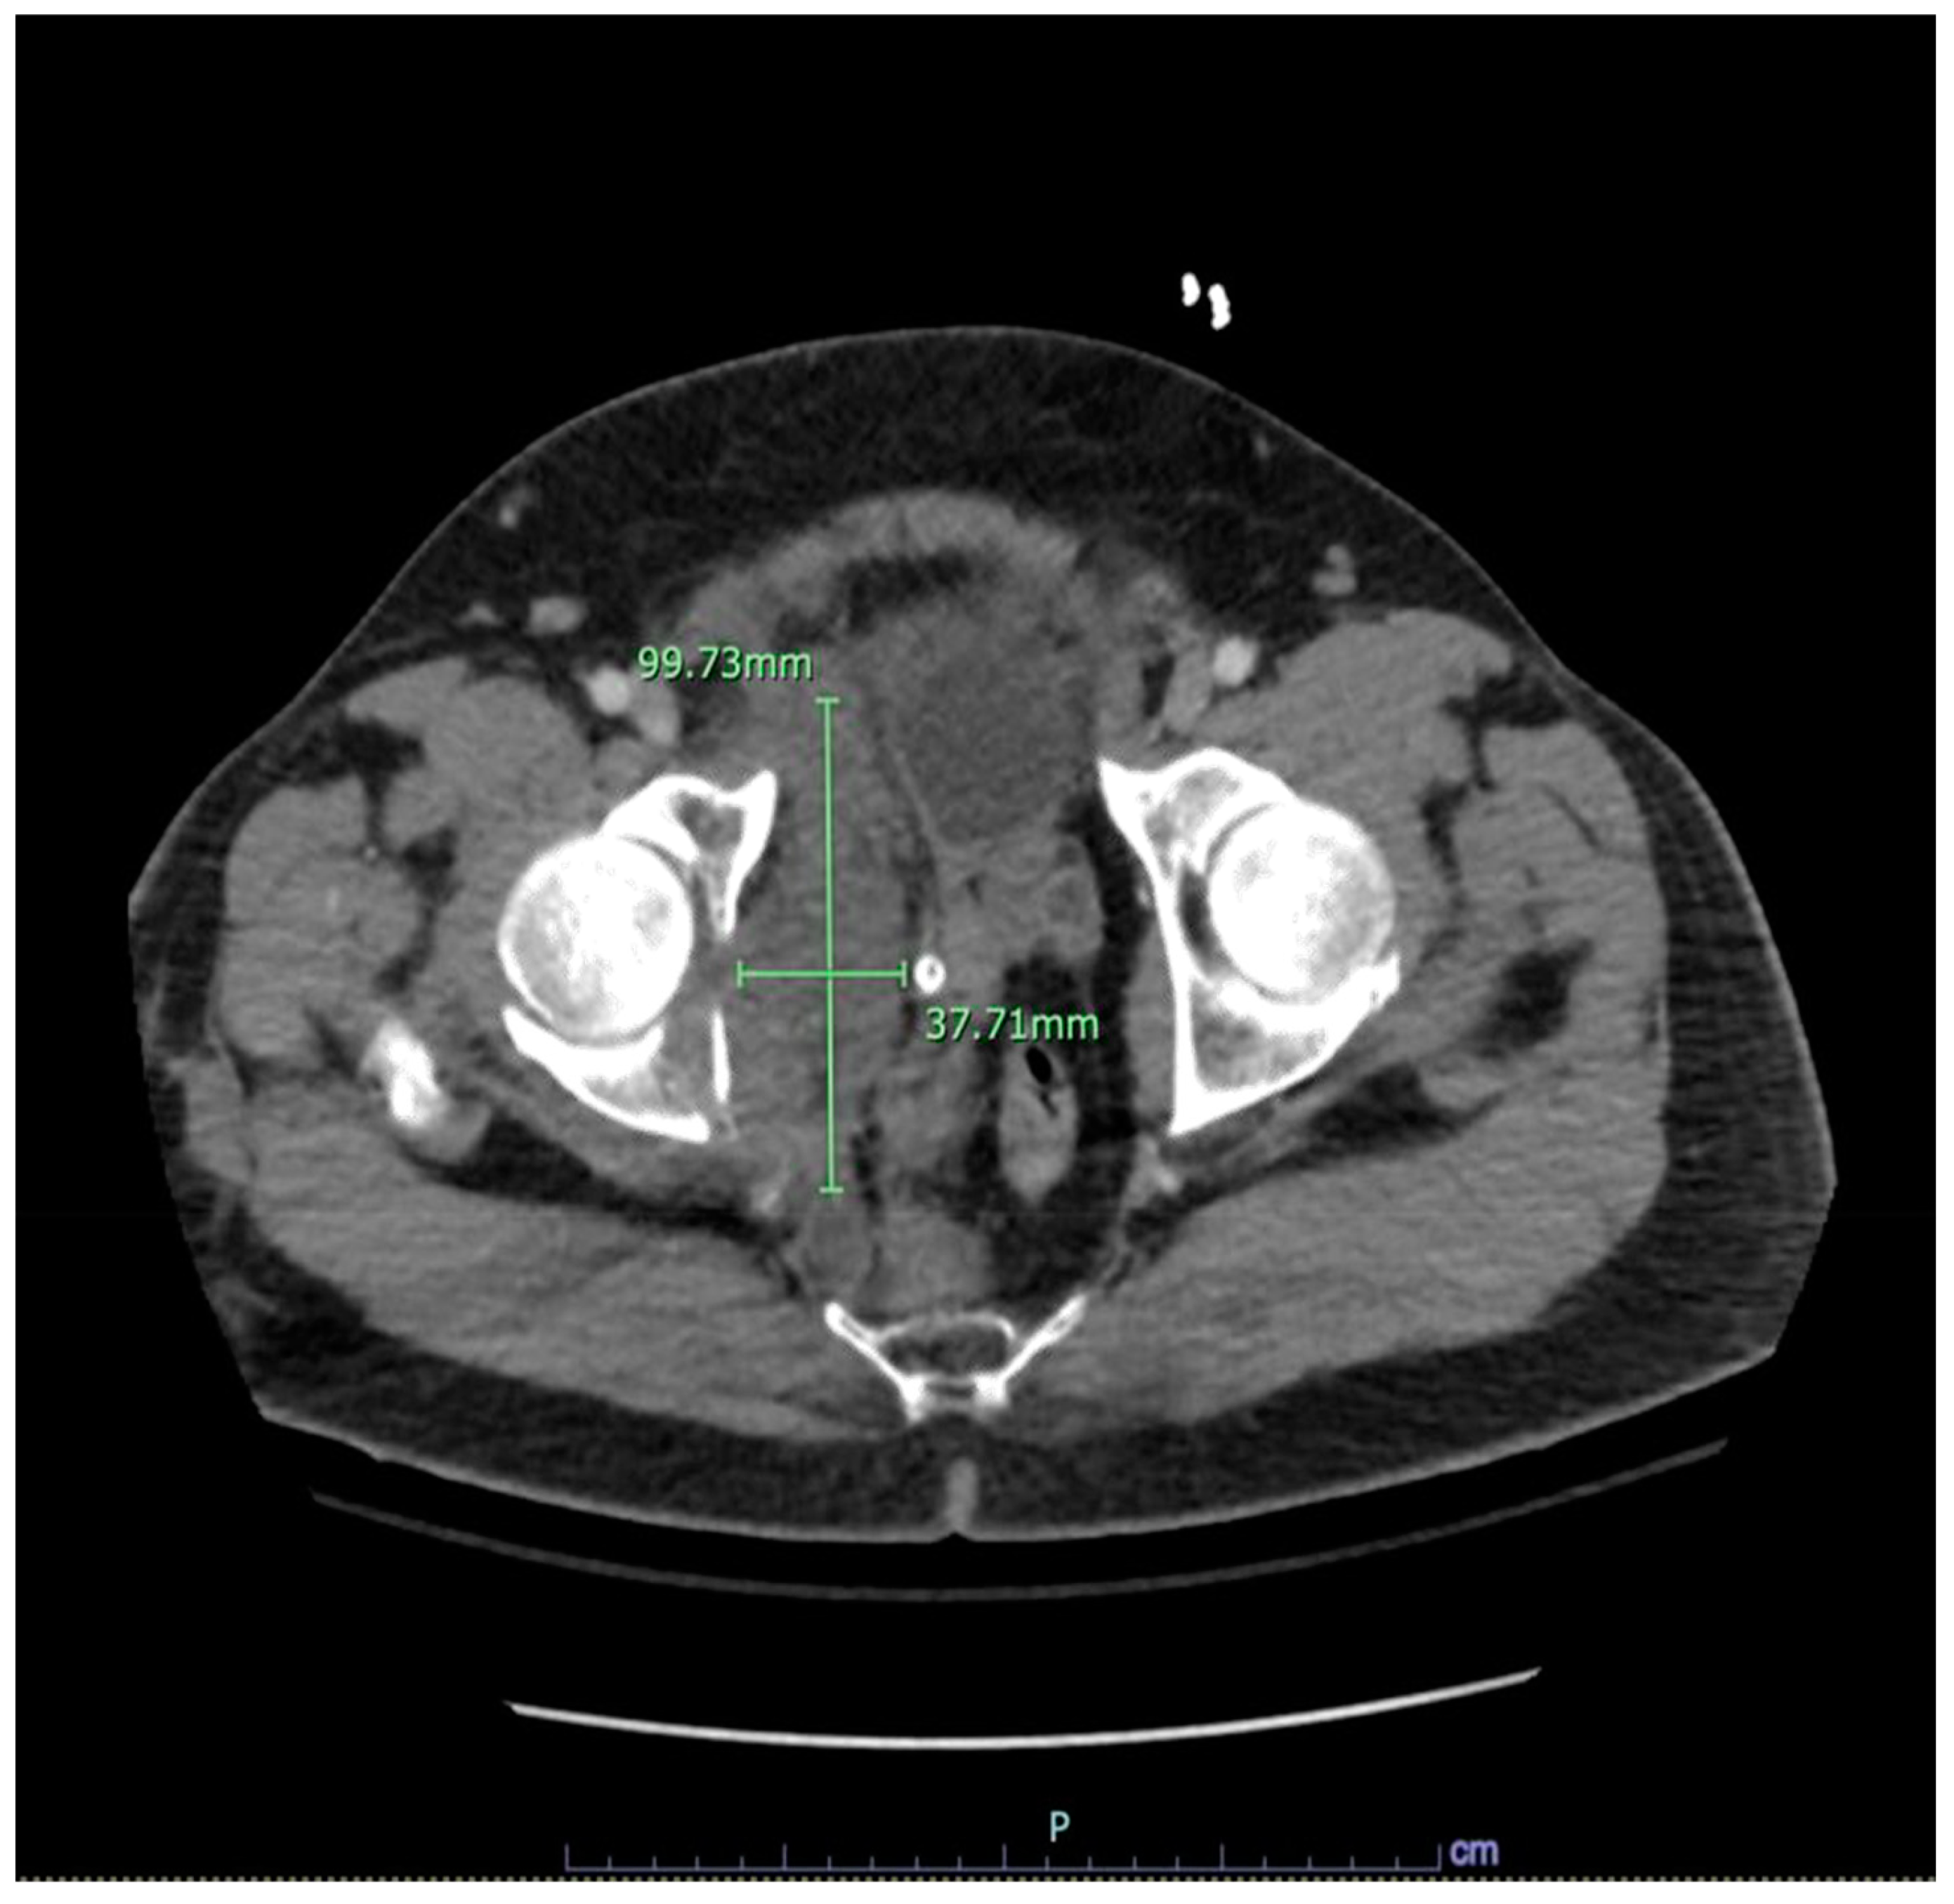

Figure 2. Acute thoracic aortic injury, pseudoaneurysm, with associated periaortic hematoma detailed above. 2. Multiple right rib fractures detailed above. 3. Right pelvic fractures involving the right acetabulum, right pubic rami and right pubic symphysis with an associated right pelvic sidewall hematoma measuring 10 x 5 cm without evidence of active hemorrhage. 4. Suspected midline pancreatic grade 1 injury/laceration.